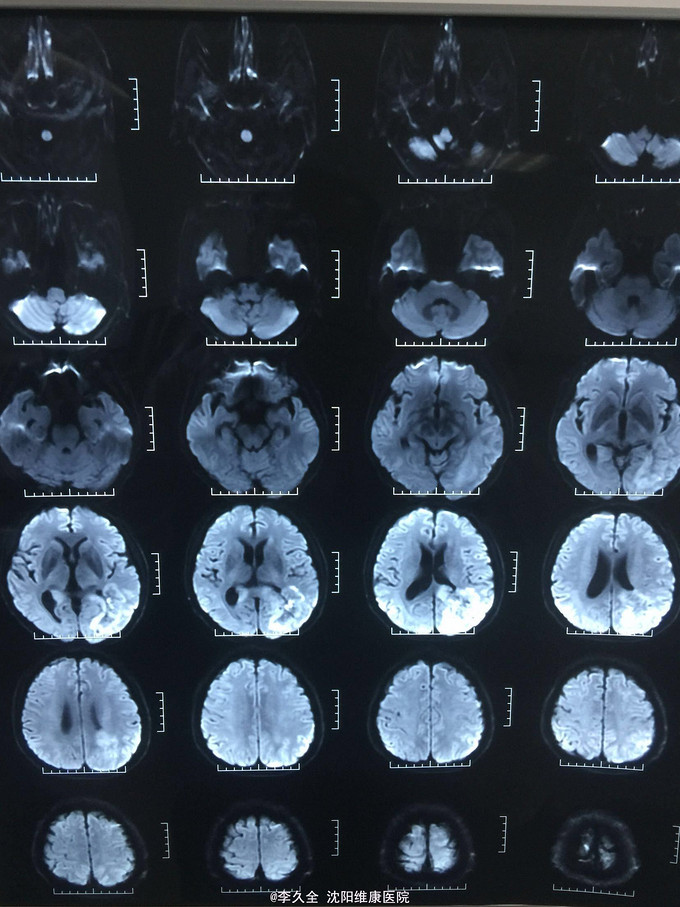

男,62岁,以头晕、视野缺损、记忆力减退、失写、失算7个月入院! 现病史:去年7月出现头晕,就诊于医院,行头CT:代诉未见异常,口服药物无效,后出现右侧视野缺损,走路撞墙、撞门,就诊于当地医院、北京协和医院,考虑“㬵质瘤”,近3个月出现近事遗忘为主,平时写字不会,计算力下降,不认识人! 既往史:2型糖尿病5年!

查体:BP:150/80mmHg,心肺腹无异常。神清,不能言语,失写、失算、失认,双曈孔等大正圆,直径3.0mm,光敏,四肢能够活动,右侧肌张力增高,巴氏征R+L-,颈强3横指,克氏征阳性! 影像MR:

1.颅内占位,胶母可能大! 2.2型糖尿病